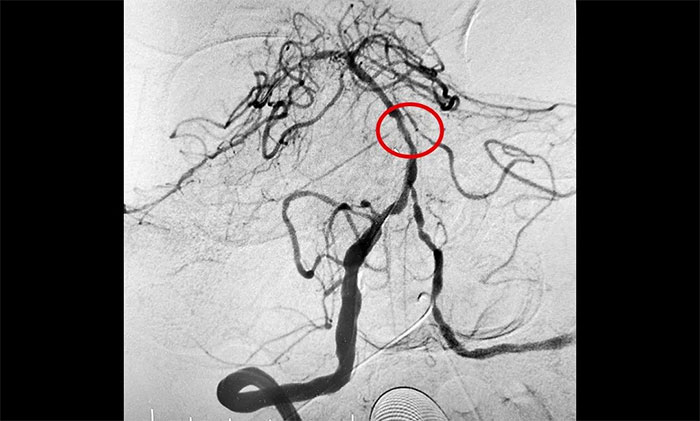

▲ 基底動脈順利開通

11月20日,經(jīng)過充分的準備工作,席剛明教授團隊在介入團隊協(xié)助下順利實施了手術。術中兇險的就是反復球囊擴張狹窄,如果掌握不好擴張球囊的位置和擴張速度,勢必造成更復雜的血管夾層甚至出血。歷時3個多小時奮戰(zhàn),席剛明教授憑借豐富的臨床經(jīng)驗及精準的手法順利地于基底動脈狹窄處進行球囊擴張,患者基底動脈得以完全開通,手術獲得圓滿成功,打開了患者的“生命通道”。

術后,患者順利蘇醒,無新發(fā)功能缺損,肢體無力、肢體麻木癥狀得到改善。